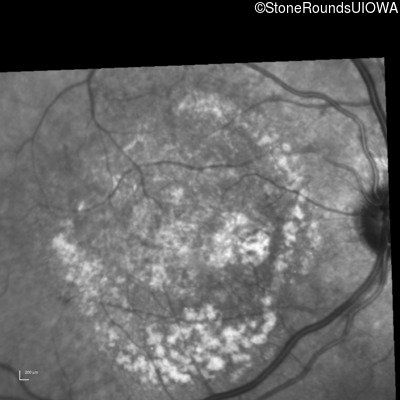

Fluorescein Angiography - Right - 20/250